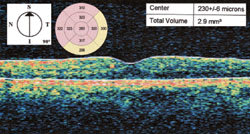

Figure 4. OCT after 2 subthreshold micropulse diode laser treatments (8 months after the first treatment). The central foveal thickness has decreased from 230 μm to 207 μm. The perifoveal thickness within the 3.45 mm radius (within the 2 rings around the fovea) has also decreased when compared to the prelaser OCT (Figure 2). |